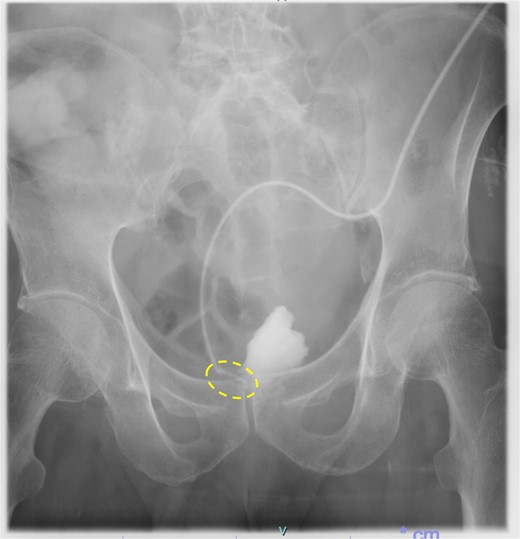

Following reoperation, although drainage led to shrinkage of the fistula, it persisted after 2 months (Fig. 2). Hence, we decided to close the fistula using endoscopic clips. Gastrografin was injected through the drain under colonoscopy and radiography, and bleeding was observed at the suspected fistula orifice, which was provisionally clipped using a MANTIS clip. Gastrografin was injected again, and definitive clipping was completed confirming the successful fistula closure (Fig. 3). The patient was discharged after 2 days. The drain was withdrawn about 3 cm on day 9 after discharge. On day 15, gastrografin injection under radiography revealed recovery of the fistula (Fig. 4). Thereafter, the drain was withdrawn cautiously about 2 cm every 2–3 days to prevent residual fistula formation and removed completely on day 29. Ileostomy closure was performed 6 months after the initial surgery. The patient was discharged without complications on postoperative day 7.

On day 15 after clipping, gastrografin injection under radiography reveals the fistula tends to recover.